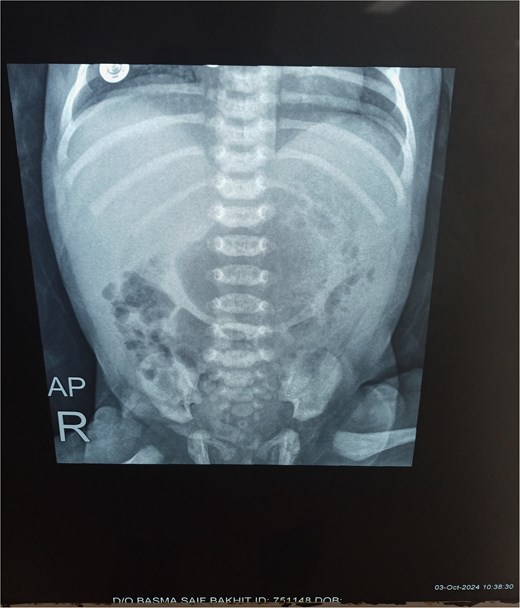

Chest X-ray was normal (Fig. 1). A water-soluble contrast meal was performed (Fig. 2) and the contrast arrested at the gastric antrum for 45 min. Then there was normal opacification of the duodenum and jejunum on follow-up films after 1.15 and 1.3 h. A complementary ultrasound (US) was done along with the contrast study and it showed a thick mucosal fold (4 mm) at the gastric antrum situated 1 cm away and on the left side of the duodenum. The pyloric canal was open and patent and had a normal wall thickness (1.5 mm) excluding hypertrophic pyloric stenosis.

The contrast study done pre-operatively showing the progression of the contrast in the digestive tract of the neonate.